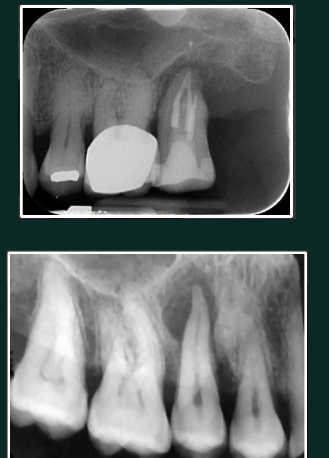

Periapical cemento-osseous dysplasia (PCOD)

Mixed lesions

occurs in vital teeth

anterior mandible common

3 stage progression

RL

Mixed

RO with thin RL border

often bilateral and symmetrical

Fibrous dysplasia)

ground glass look

borders blend into surrounding bone

loss of lamina dura

often unilateral expansion

Paget’s disease

cotton wool pattern

patchy irregular RO regions

may cause increased alveolar ridge size

possible increased spacing between teeth

linked with this disease (late stage)